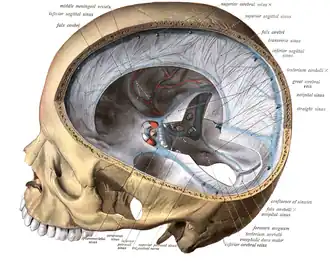

Das Blut fließt über ein System von Venen und Sinus aus dem Gehirn in die großen Halsvenen (Jugularvenen) ab (vgl. nebenstehende Abbildung).

Von der Hirnrinde (Kortex) fließt es über oberflächliche Venen in die Sinus: vom Frontal- und Parietallappen führen die Venae superiores zum Sinus sagittalis superior, vom Schläfenlappen leiten die Venae inferiores (in der Abbildung nicht dargestellt) das Blut in die Sinus transversi. Blut aus dem Inneren des Großhirns (u. a. Marklager, Basalganglien), dem Zwischenhirn und von der Hirnbasis fließt zum Großteil über die Vena magna cerebri in den Sinus rectus ab.[20] Es gibt mehrere Anastomosen, also Querverbindungen zwischen den verschiedenen Abflussgebieten. Die Anatomie kann von Mensch zu Mensch unterschiedlich sein.[5]

Ein Blutgerinnsel (Thrombose) entsteht, wenn das Gleichgewicht aus thrombusbildenden (prothrombotischen) und thrombuslösenden (thrombolytischen) Prozessen im Blut in Ungleichgewicht gerät und die thrombusbildenden Prozesse überwiegen. Meistens geschieht dies zuerst in einem Sinus. Von dort breitet es sich durch die weitere Anlagerung von Blutplättchen in die einmündenden Venen aus,[11] aber bei vielen Patienten bilden sich die Blutgerinnsel in Sinus und Venen auch gleichzeitig aus.[15] Die am häufigsten betroffenen Gefäße sind die Sinus transversi (86 %) und der Sinus sagittalis superior (62 %), mit Abstand folgen die Venen der Hirnrinde (17 %), der Sinus rectus (18 %) und die darin mündende V. magna cerebri und andere innere Hirnvenen (11 %).[15]